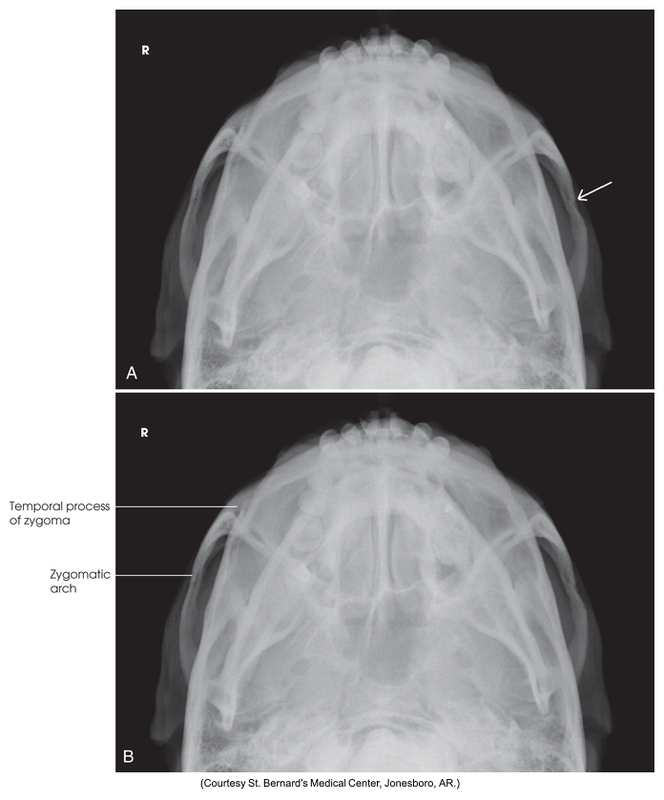

Submentovertical of the cranial base - Schuller method

Submentovertical of the zygomatic arches

Submentovertical of cranial base - Schuller method

Submentovertical of zygomatic arches